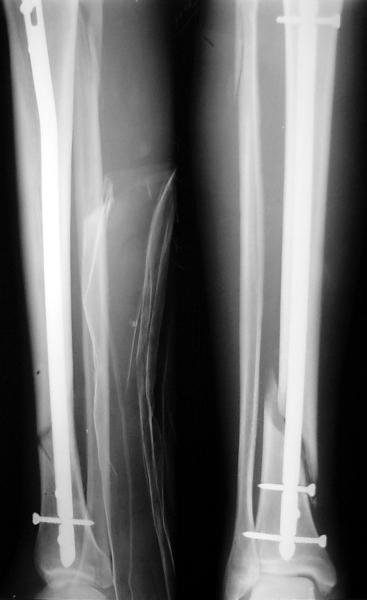

Как мне показать пример? Фото стоящего на одной оперированной конечности пациента? O! Пример, подвигнувший нас на некоторое изменение технологий. Пациент этот ходил с полной нагрузкой вопреки рекомендациям. В качестве подтверждения - сломанный проксимальный статический винт к 1 мес., а к 2 мес. - все остальные. Сейчас мы перешли на более fool-proof остесинтез.

Ok. А также и следующий, в 3 месяца.

Это наглядная демонстрация возможности ранней полной нагрузки при нестабильном по оси повреждении, причем не в самых благоприятных механических условиях - при плохом сопоставлении, со слабым фиксатором.

Сверху - один статический винт, а снизу - три. Что раньше сломается? Конечно, он потом и нижние сломал, и Вы правы, если бы верхний динамичесий винт уже уперся бы в нижний край отверстия, будь гвоздь подлинее, перфорировал бы сустав как пить дать.

Как я уже говорил, мы сделали выводы из этого и других подобных случаев. Очевидно, решений проблемы два - либо уменьшить нагрузку, либо увеличить прочность фиксатора. Первое решение работает не со всеми больными, так что пошли по второму пути - мы больше не используем гвозди с запирающими винтами диаметром 4 мм.